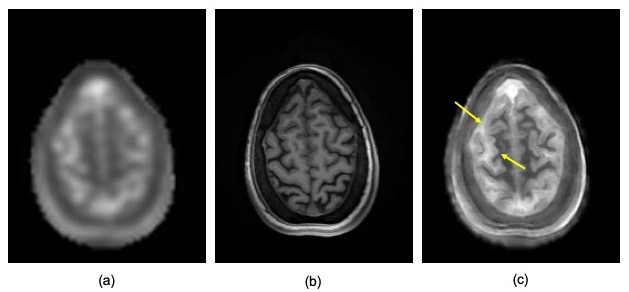

Figure 3: Single slice from the (a) SW TPI input sodium image, (b) high-resolution T1 scan and (c) AGR result for the same data set in figure 2. These images clearly illustrate clear separation between the CSF, gray matter and white matter compartments of the brain (arrows).